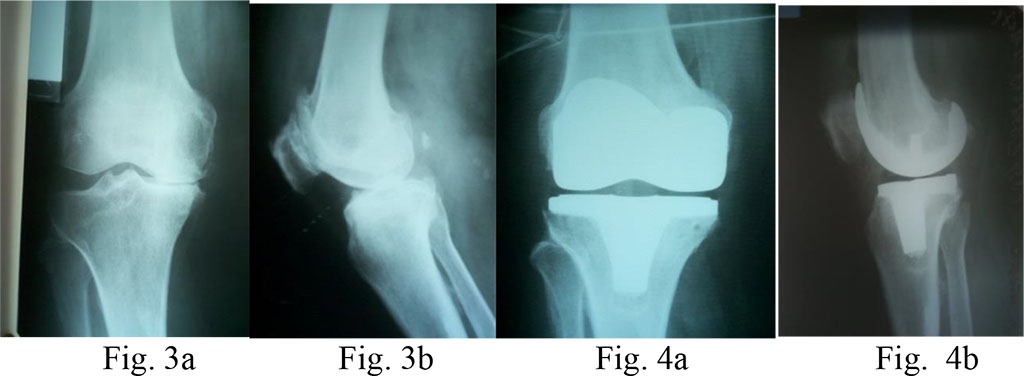

Diagnosis: knee osteoarthritis on the right, IV stage according to Kellgren&Lawrence (1957); varus deformity of the joint; expressed pain syndrome.

Surgical treatment: total arthroplasty of the right knee with PCL-preserving system (Fig. 3a, b and 4a, b)

Diagnosis: knee osteoarthritis on the left, IV stage according to Kellgren&Lawrence; varus deformity of the joint, 15o flexion contracture of the left knee.

Surgical treatment: total arthroplasty of the left knee with an LPS prosthesis (without preservation of the PCL) (Fig. 5a, b and 6a, b)